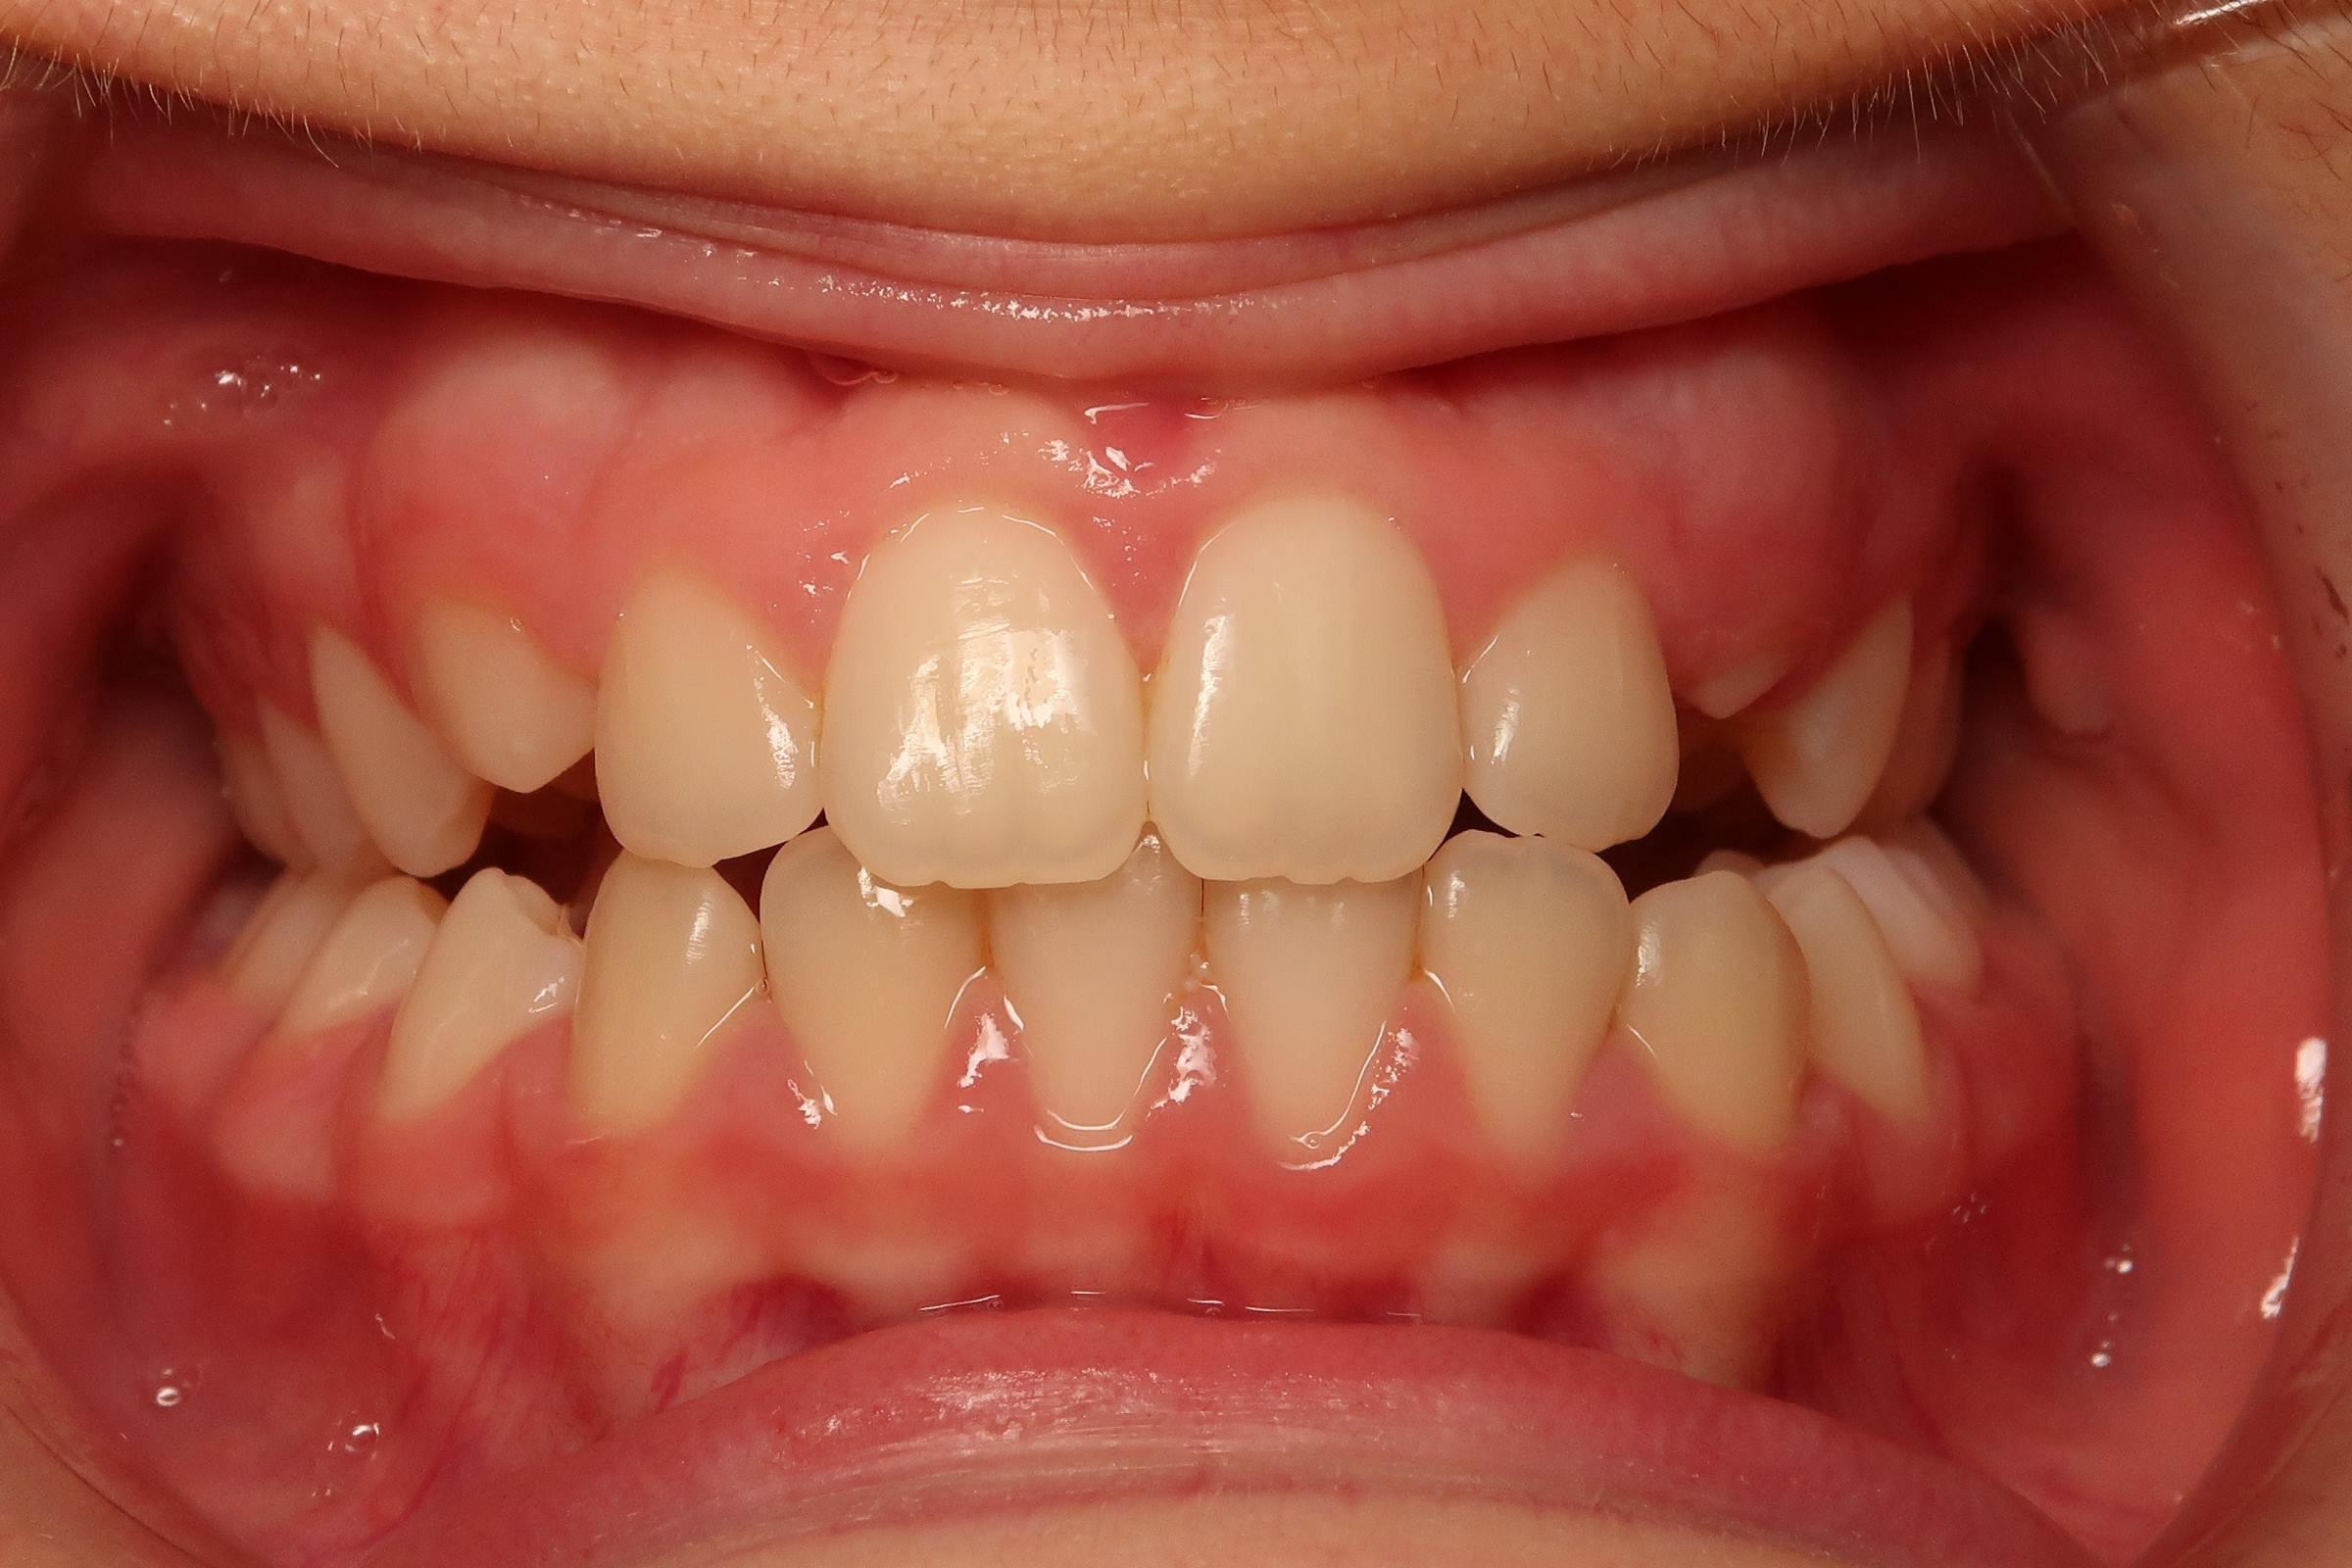

25. bout à bout anterieur 6 ans

dents du haut bout à bout par rapport à celle du bas

bilan début et en cours de traitement